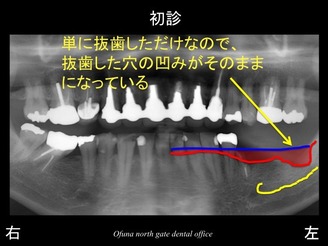

以下が初診時です。

下顎の左側の歯が抜けてしまって噛めないとのことで来院されました。

下顎左側の奥歯が2歯分欠損していました。

骨吸収の状態を線で書いたのが以下のレントゲンになります。

さらに分かりやすくするために 骨吸収部位を赤色の領域で表します。

特に一番奥では、骨吸収が非常に大きいのが分かるかと思います。

通常、インプラント治療を前提として抜歯した場合には、抜歯直後に抜歯した穴ができるかぎり 早く骨で埋まるような治療法を行います。

単に抜歯しただけでは、穴は埋まりにくいのです。

抜歯した穴に骨が再生しやすい行う治療法をソケットプリザベーション法 と言います。

このソケットプリザベーション法 を行うかどうかが今後のインプラント治療に大きく影響するのです。

今回の症例では、下顎の一番奥の歯は、他歯科医院で抜歯されました。

おそらくソケットプリザベーション法 は行っていないと考えられます。